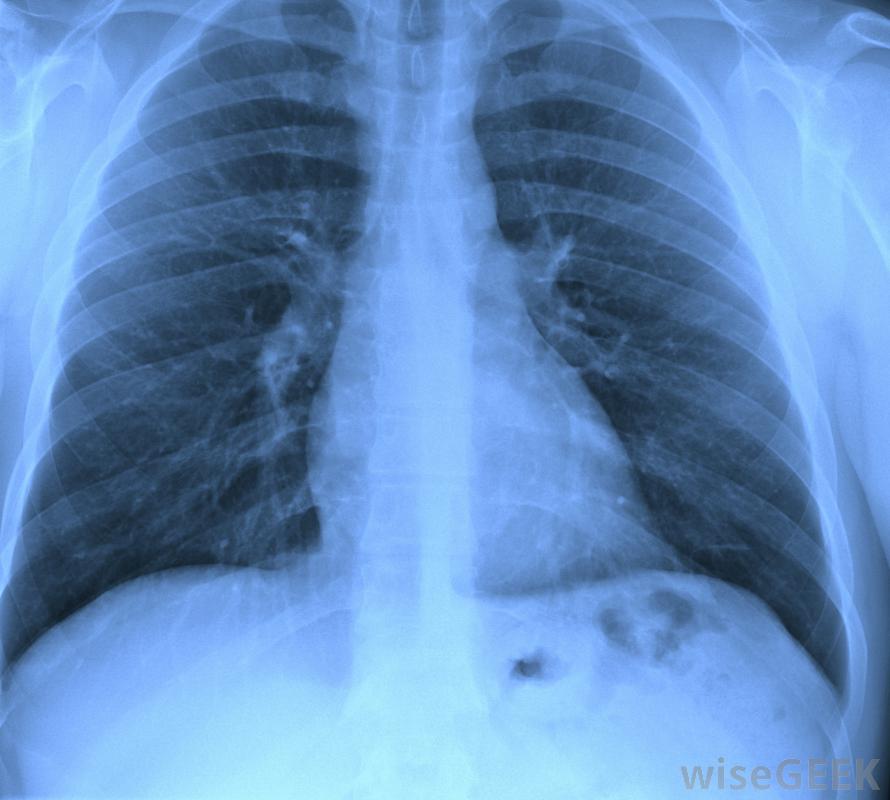

受疤痕组织影响的肺部的X光片个体在接受肺癌的放射治疗时,肺部的肿瘤会受到旨在吞噬肿瘤的放射物的轰击,然而,这样做也会损害附近的血管和气囊。随着这些区域的愈合,通常会形成疤痕组织。当停止辐射并切除肿瘤时,疤痕就会形成组织将停止形成。

肺纤维化可能导致肺部瘢痕组织